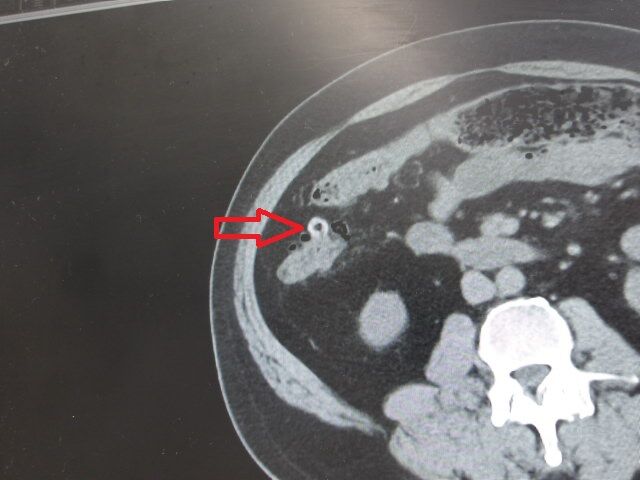

ç¹Â¡ÉÕ¶á¤ÎÆæ¤ÎO¥ê¥ó¥°

Á°²ó;¤ê¤ÎÄˤµ¤«¤é³Ý¤êÉÕ¤±°å¤Ø¹Ô¤¶ÛµÞ¤ÇCT»£±Æ¤ò¤·¤ÆÌã¤Ã¤¿²èÁü¤ÎµÏ¿¤ò

;¤ê¤Î¥·¥ç¥Ã¥¯¤«¤é¼Ì¿¿»£±Æ½ÐÍè¤Ê¤«¤Ã¤¿¤Î¤Ç

ºòÆü¤Î¼õ¿Ç»þ¤Ë¼ç¼£°å¤Ë¤ª´ê¤¤¤ò¤·¤Æ

²èÁü¤ò½Ð¤·¤Æ¤â¤é¤¤¡¢¼Ì¿¿»£±Æ¤ò¹Ô¤Ã¤Æ

ÀâÌÀ¤â¤Á¤ã¤ó¤Èʹ¤¤¤Æµï¤Ê¤«¤Ã¤¿¤Î¤Ç

ÁÛÄêÉÂ̾¤òʹ¤¤¤Æ¡¢º£¸å¤Î¼£ÎÅÊýË¡¤âÁêÃ̤·

©»Ò¤Ë¤â²èÁü¤òÁ÷¿®¡¢Â©»Ò¤Î¿ÇÃÇ·ë²Ì¤âƱ¤¸¤Ê¤Î¤Ç¤¹¤¬

¼ç¼£°åƱÍÍ¡¢²èÁü¤«¤éȽÃǤ¹¤ë±ê¾É¤ÎÅٹ礤¤¬Ä㤤¤È¸À¤¦¡Ä

¼è¤ê¹ç¤¨¤º»à¤Ì»ö¤Ï̵¤µ¤½¤¦¤Ê¤Î¤Ç¡¢ÄˤߤϲæËý¤¹¤ë»ö¤Ë¤·¤Þ¤¹¡ª

¼ç¼£°å¤Î¿ÇÃǤÈ©»Ò¤Î¿ÇÃÇ¤ÏÆ±¤¸¸«²ò¤ÇÉÂ̾¤ÏÂçIJ¤Î¡Ö·Æ¼¼±ê¡×¤È¸À¤¦»ö¤é¤·¤¤¡Ä

²Ç¤Ï£Ï¥ê¥ó¥°¤ò°û¤ß¹þ¤ó¤À¤Î¤«¤È»×¤Ã¤¿¤é¤·¤¤¤ï£÷